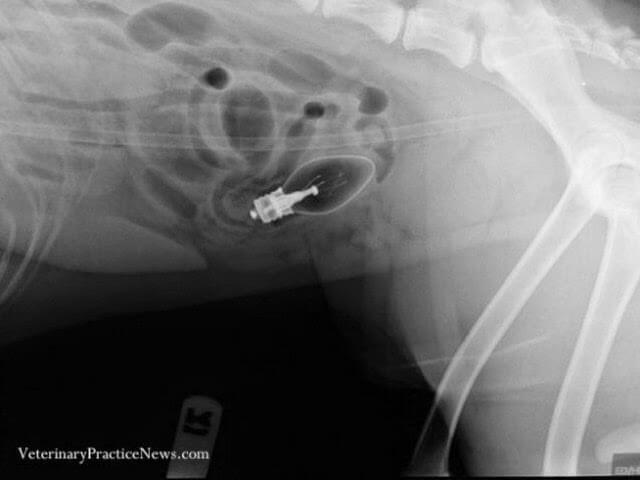

Continue LendoEles comeram o quê? Uma competição promovida pela America’s Veterinary Practice News onde os veterinários enviam raios-X de animais com coisas estranhas presas dentro de seus corpos. Estes são alguns dos vencedores. Não se preocupe, todos os animais foram tratados apropriadamente e eles estão bem e com fome de novo. Primeiro lugar: Mais […]